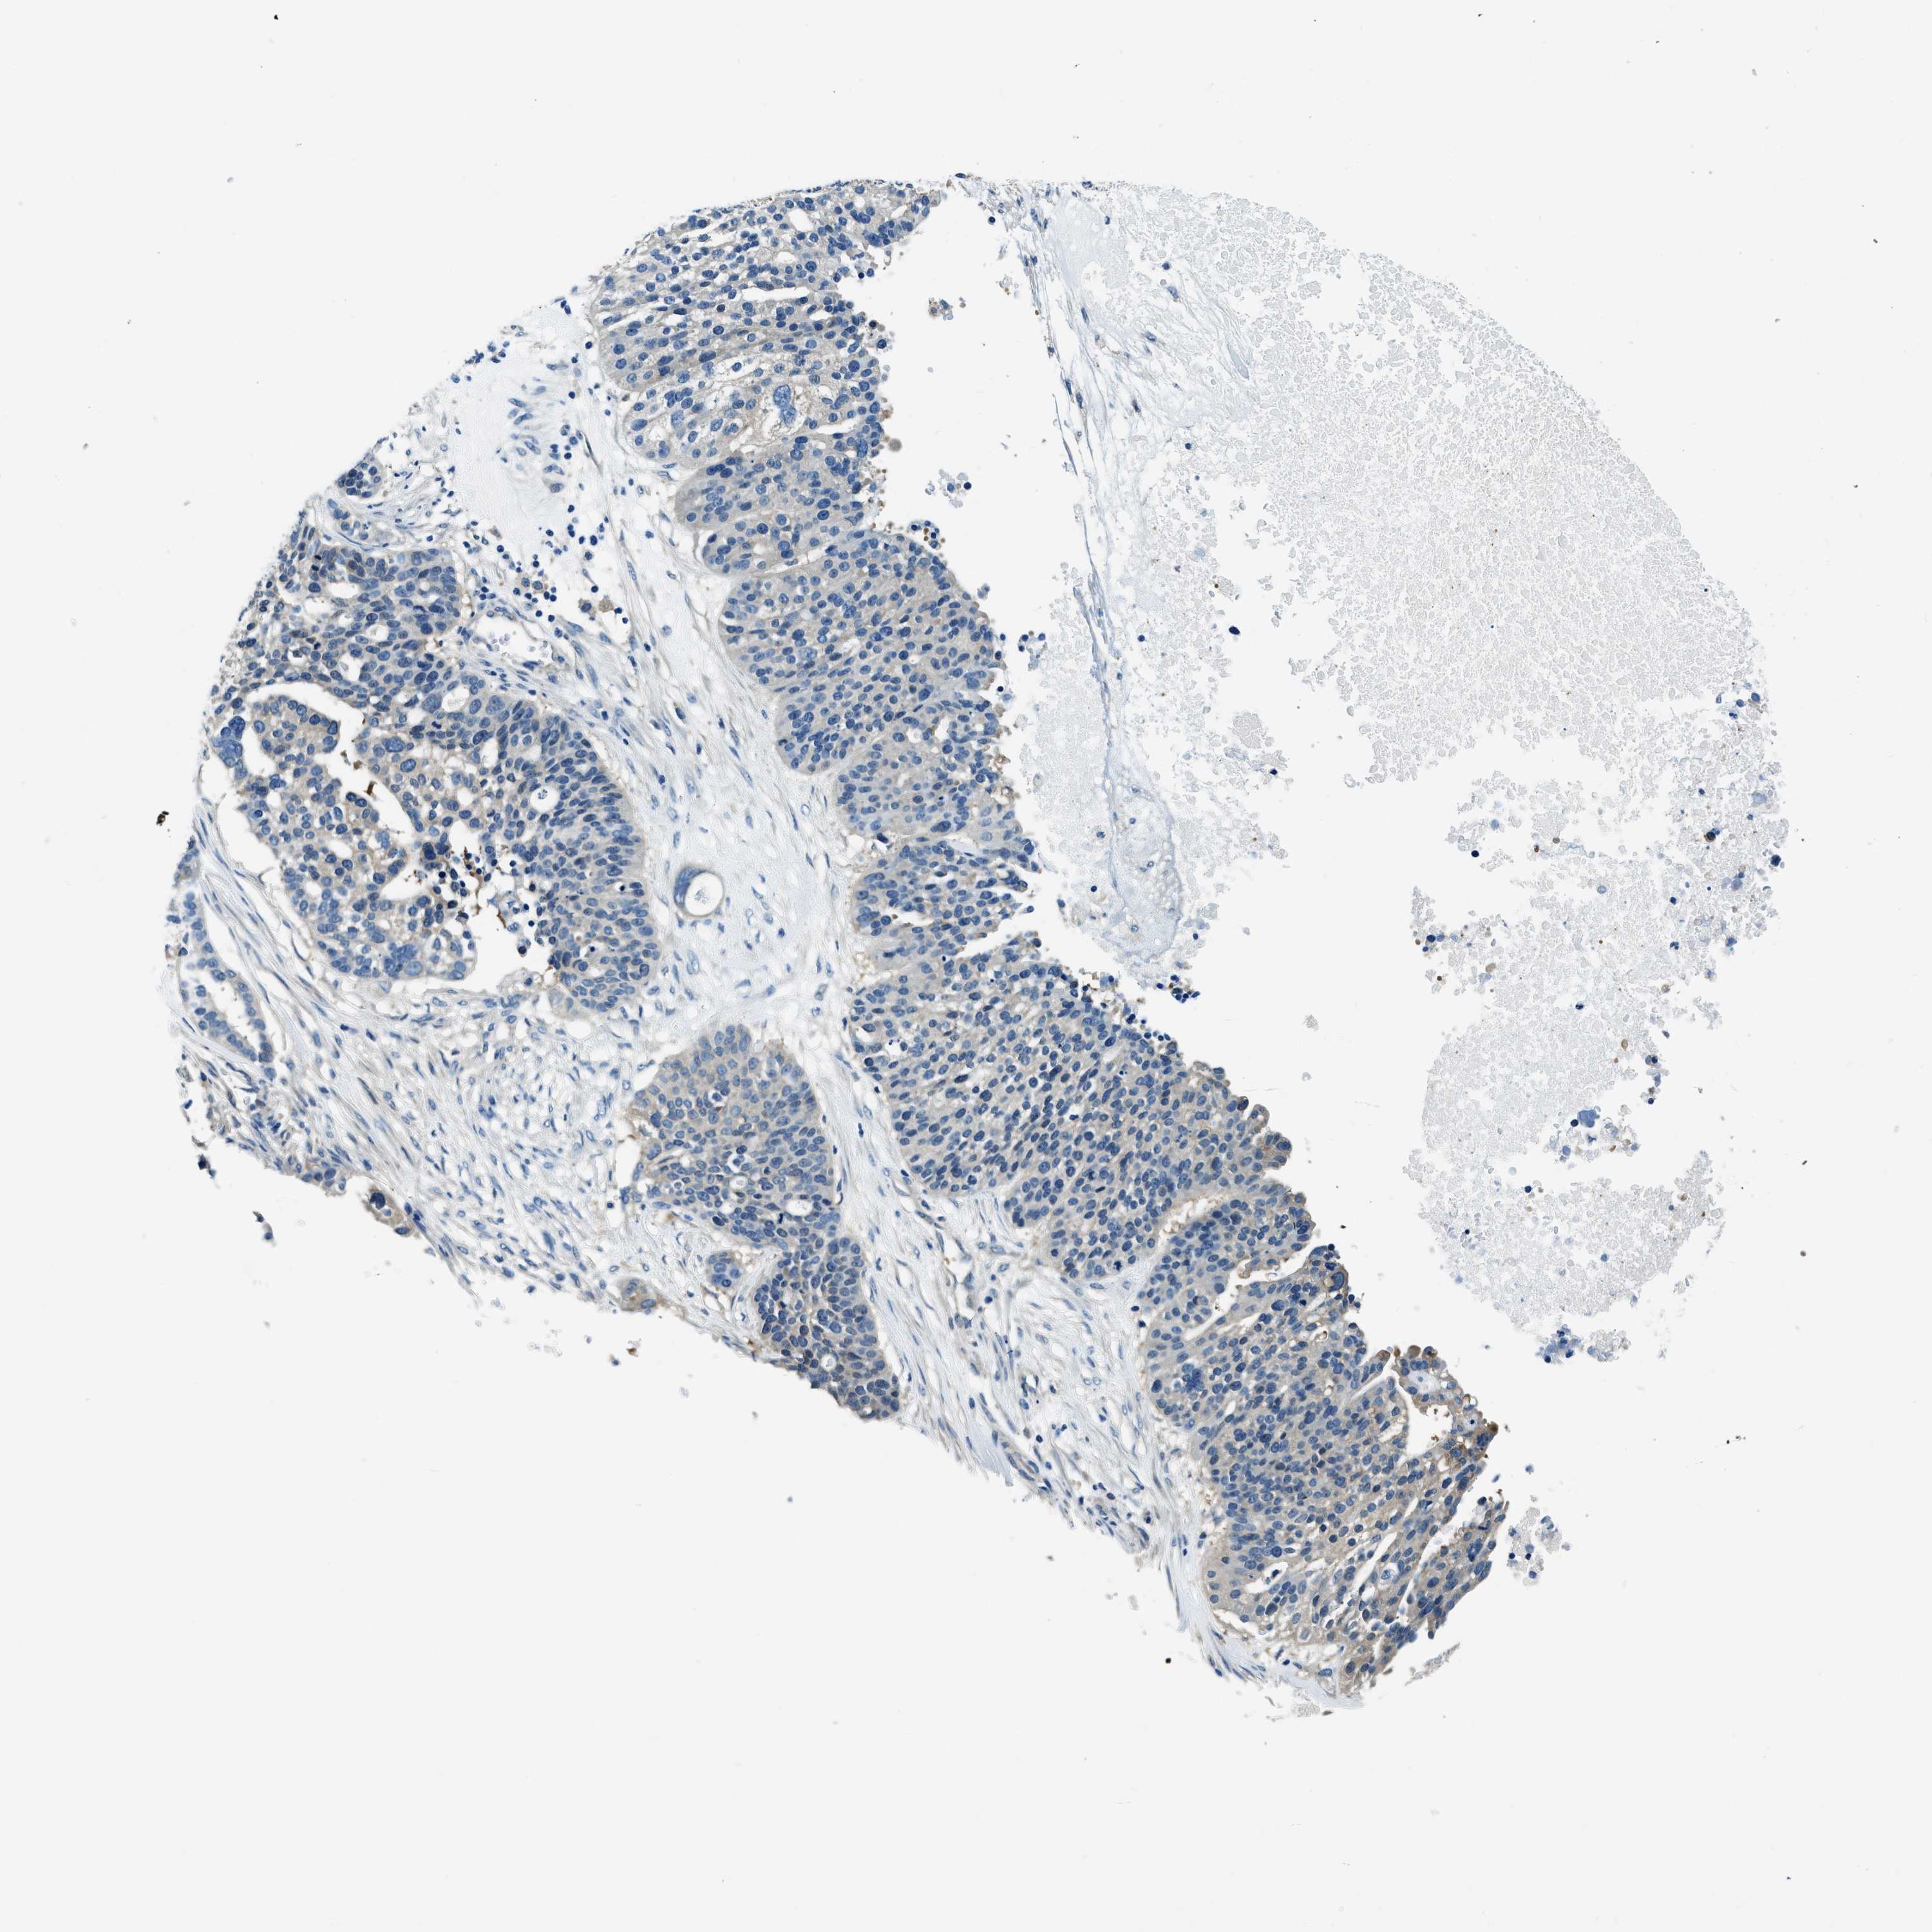

OVARIAN CANCER - Protein expressioni

A mouse-over function shows sample information and annotation data. Click on an image to view it in a full screen mode. Samples can be filtered based on level of antibody staining by selecting one or several of the following categories: high, medium, low and not detected. The assay and annotation is described here.

Note that samples used for immunohistochemistry by the Human Protein Atlas do not correspond to samples in the TCGA dataset.

Antibody stainingi

Antibody staining in the annotated cell types in the current human tissue is reported as not detected, low, medium, or high, based on conventional immunohistochemistry profiling in selected tissues. This score is based on the combination of the staining intensity and fraction of stained cells.

Each image is clickable and will lead to virtual microscopy that enables deeper exploration of all samples and also displays staining intensity scores, fraction scores and subcellular localization as well as patient and tissue information for each sample.

Antibody HPA018116

Staining

High

Medium

Low

Not detected

Intensity

Strong

Moderate

Weak

Negative

Quantity

>75%

75%-25%

<25%

None

Location

Nuclear

Cytoplasmic/membranous

Cytoplasmic/membranous,nuclear

Cystadenocarcinoma, serous, NOS

Carcinoma, endometroid

Cystadenocarcinoma, mucinous, NOS

Carcinoma, NOS